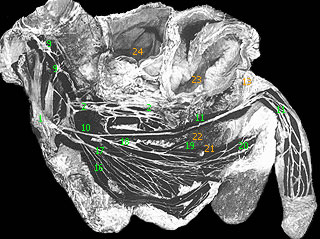

Срамной (половой) нерв(n. pudendus (pudendalis); срамное сплетение, plexus pudendus; S1-S4) представляет собой каудальный (хвостовой) отдел крестцового сплетения (начало: plexus sacralis) и связан с ним несколькими ветвями. Нерв лежит под нижним краем грушевидной мышцы на передней поверхности копчиковой мышцы; по его передней поверхности проходят в продольном направлении латеральные крестцовые сосуды (vasa sacralia lateralia).

Срамной нерв связан с крестцовым сплетением и нижележащим копчиковым сплетением, а также несколькими нервными стволиками с вегетативным нервным сплетением (нижним) подчревным сплетением (plexus hypogastricus (inferior)). Своими ветвями срамной нерв принимает участие в иннервации внутренних органов полости малого таза, наружных половых органов, мышц промежности и кожи области промежности, слизистую оболочку мочеиспускательного канала. Топографически нерв можно разделить на две части: внутритазовую и внетазовую (промежностную).

Ветви внутритазовой части срамного нерва

1. Мышечные ветви отходят от нерва в полости малого таза и направляются к мышце, поднимающей задний проход (m. levator ani), и копчиковой мышце (m. coccygeus) (эту мышцу может иннервировать ветвь, общая с m. levator ani).

2. Средние прямокишечные нервы, соединяясь с ветвями подчревного сплетения, подходят к той части прямой кишки, которая располагается выше m. levator ani; ряд нервных стволиков входит в толщу этой мышцы.

3. Нижние пузырные нервы, так же как и предыдущие, соединяются с ветвями подчревного сплетения и следуют к области дна мочевого пузыря, к мышце, сжимающей мочевой пузырь (m. sphincter vesicae).

4. Влагалищные нервы, соединяясь с ветвями подчревного сплетения, направляются к верхним отделам влагалища.

Ветви внетазовой (промежностной) части срамного нерва

Срамной нерв выходит из полости малого таза в сопровождении медиально лежащих от него внутренних срамных сосудов (vasa pudenda interna), через щель под грушевидной мышцей. Далее он ложится на заднюю поверхность седалищной ости (spina ischiadica), огибает ее и, пройдя через малое седалищное отверстие (foramen ischiadicum minus), возвращается в полость таза, располагаясь ниже мышцы, поднимающей задний проход (m. levator ani), в седалищно-ректальном углублении (fossa ischiorectalis), где он идет по ее латеральной стенке, в толще фасции внутренней запирательной мышцы.

В седалищно-ректальном углублении срамной нерв делится на свои ветви:

· а) Нижние прямокишечные нервы (nn. rectales inferiores) располагаются наиболее медиально, следуют к промежностной части прямой кишки, наружному сфинкетру заднего прохода (m. sphincter ani externus) и к коже области заднепроходного отверстия.

· б) Промежностные нервы (nn. perineales) следуют в сопровождении сосудов промежности (vasa perinei) и являются наиболее поверхностным из концевых ветвей срамного нерва.

· в) Задние мошоночные нервы (nn. scrotales posteriorei) или задние губные нервы (nn. labiates posteriores) - поверхностно лежащая группа ветвей, направляющихся к коже области промежности и к коже задней поверхности мошонки (больших срамных губ); эти нервы соединяются с нижними прямокишечными нервами, а также с промежностными ветвями заднего кожного нерва бедра.

· г) Мышечные ветви - более глубоко располагающиеся нервные стволики, которые следуют к передним отделам наружного сфинкетра заднего прохода (m. sphincter ani externus), поверхностной поперечной мышцы промежности (m. transversus perinei superficialis), луковично-губчатой мышцы (m. bulbospongiosus) и к седалищно-пещеристой мышцаы (m. ischiocavernosus).

· д) Дорсальный нерв полового члена (n. dorsalis penis) или дорсальный нерв клитора (n. dorsalis clitoridis) является верхней ветвью срамного нерва. Он следует в сопровождении артерии полового члена (короткой ветви внутренней срамной артерии) по внутренней поверхности нижней ветви седалищной и лобковой костей и, проходя через мочеполовую диаграмму, ложится вместе с дорсальной артерией мужского полового члена (a. dorsalis penis) или клитора (clitoridis) на спинку мужского полового члена или клитора у женщин, где разветвляется на свои концевые ветви в коже и в пещеристых телах мужского полового члена, достигая его головки, а у женщин достигает больших и малых срамных губ. На своем пути нерв посылает стволики к m. transversus perinei profundus, m. sphincter urethrae membranaceae и к нервному пещеристому сплетению (plexus cavernosus penis (clitoridis)).

1 - крестцовое сплетение (plexus sacralis); 2 - нижнее подчревное (тазовое) сплетение, передняя часть (plexus hypogastricus inferior (pars ventralis)); 3 - нижнее подчревное (тазовое) сплетение, задняя часть (plexus hypogastricus inferior (pars dorsalis)); 4 - прямокишечное сплетение (plexus rectalis); 5 - простатическое сплетение (plexus prostaticus); 6 - мочепузырное сплетение (plexus vesicalis); 7 - семявыбрасывающепроточное сплетение (plexus deferentialis); 8 - симпатический (пояснично-крестцовый) ствол (truncus sympathicus (truncus lumbosacralis)); 9 - пояснично-крестцовый узел симпатического ствола (ganglion lumbosacrali trunci sympathici); 10 - срамной нерв (n. pudendus); 11 - правый дорсальный нерв полового члена (ветви) (n. dorsalis penis dexter); 12 - крестцовый мыс (promontorium; сакровертебральный угол); 13 - лобковый симфиз (symphysis pubica); 14 - брюшина (peritoneum); 15 - луковично-губчатая мышца (m. bulbocavernosus); 16 - нижние прямокишечные нервы; 17 - мышечные нервы срамного сплетения; 18 - промежностный нерв; 19 - ветвь промежностного нерва к предстатетльной железе; 20 - ветвь промежностного нерва к мошонке; 21 - правая луковично-мочеиспускательная железа мочеиспускательного канала; 22 - предстательная железа; 23 - мочевой пузырь; 24 - прямая кишка; 25 - крестцовый узел симпатического ствола (ganglion sacrali (trunci) sympathici)